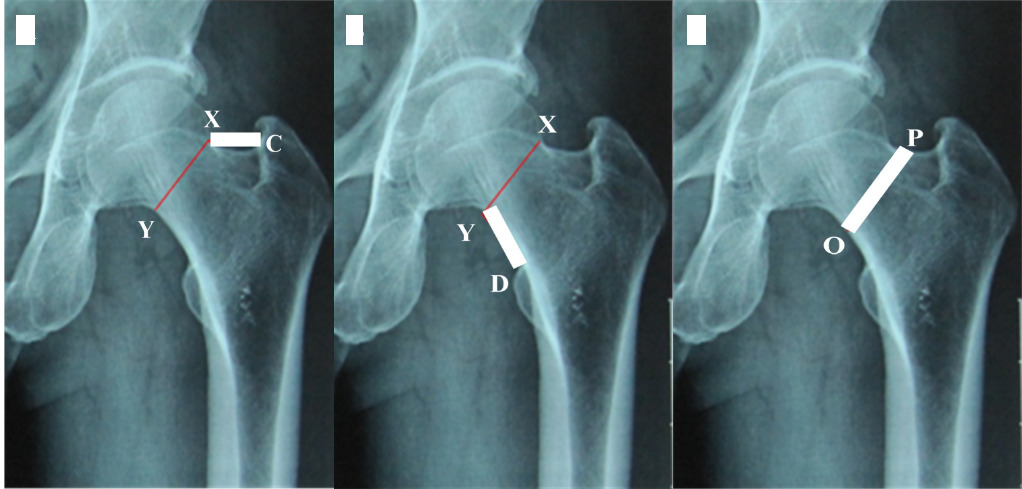

- The length of the upper border of the femoral neck The length of the upper border of the femoral neck is the distance between points X and C (Figure 2A).

- The length of the femoral neck’s lower border is the distance between points Y and D (Figure 2B).

- The distance above, below, and in the middle of the femoral neck is the distance between the two points O and P (Figure 2C).